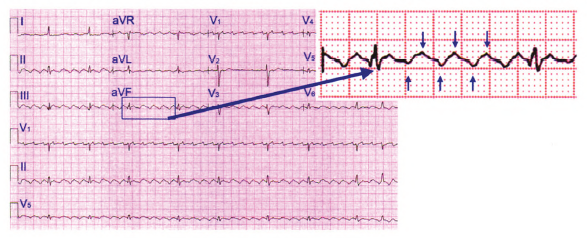

(4)F波的识别:F波在心电图Ⅱ、III、aVF和V1导联最易识别。房扑伴2:1传导时,可能一个F波与QRS波重叠,另一个F波将出现在两个QRS波之间,此时可应用Bix法则使诊断容易。此外,当V1导联存在一个低振幅锐利的心房波时将有助于房扑诊断。反复性房扑相对少见,表现为短阵房扑发作中间夹有几次窦性心律。

(2)双向锯齿波:F波多为形态一致的双向锯齿波,当房扑伴2:1下传时,整齐的心室率常为150 bpm。

(1)F波快而整齐:房扑是一种快而规整的房性快速性心律失常,F波的频率多为300 bpm(频率范围280~330 bpm)。